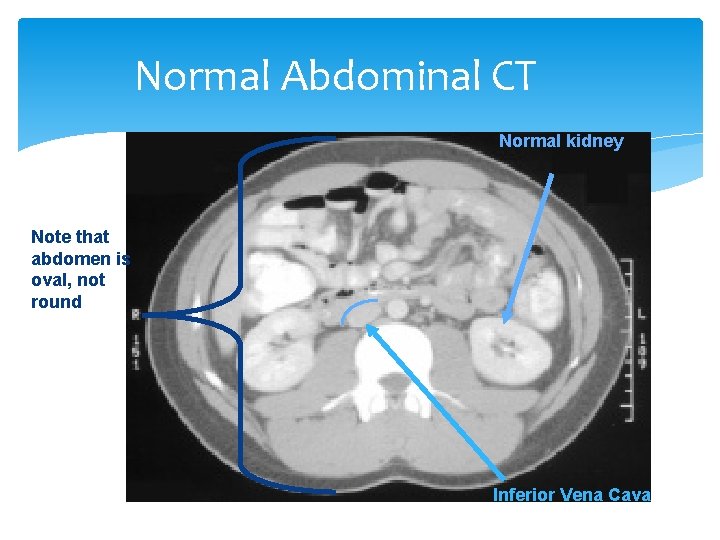

Normal Abdominal CT Normal kidney Note that abdomen is oval, not round Inferior Vena Cava